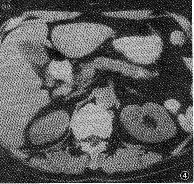

图4 慢性胰腺炎。CT平扫示胰尾部沿胰管走行分布的钙化灶,胰腺体积 缩小

2.2.1 慢性胰腺炎的胰内异常CT表现:①病变区体积:慢性胰腺炎病变区体积增大20例,其中弥漫性增大10例,局限性增大10例,正常大小9例,萎缩11例。②病变区的密度:平扫时,病变可呈等、低、低与等混杂和高密度的钙化灶,炎组中显示钙化灶者10例,占炎组总例数的25%(10/40)(图4),特别是弥漫、分散、沿胰管走向分布的钙化具有特征性,是慢性胰腺炎的重要诊断依据。③胰管扩张与胰腺囊肿:炎组显示胰管扩张15例(15/40,37.50%),其中可见扩张胰管贯通病变者12例;显示胰腺假性囊肿6例。